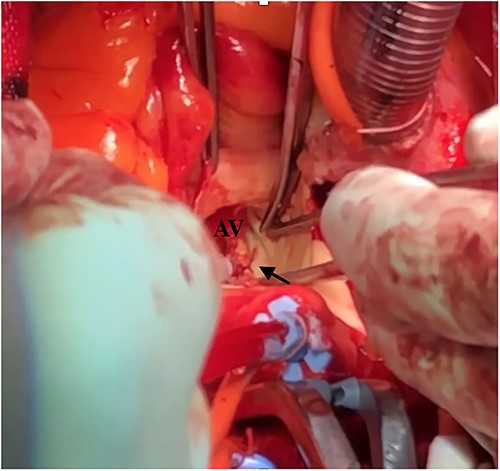

Under light sedation and local anesthesia, a 26-mm SAPIEN 3 valve was deployed with 1.5 ml less balloon inflation to avoid excessive pressure on the aortic annulus. After valve deployment, TTE revealed a small pericardial effusion. Pericardial drainage was performed, and blood was drained. Intraoperative angiography revealed a small amount of contrast leakage around the ascending aorta (Fig. 2). Transesophageal echocardiography (TEE) under deep sedation revealed a hematoma at the aortic annulus with blood inflow (Fig. 3a and b). Emergent open surgery was performed. The aorta was exposed through a median sternotomy. Cardiopulmonary bypass was established via the ascending aorta and the right atrium, and the aorta was cross-clamped. Antegrade cardioplegia was administered via an aortic root cannula, and cardiac arrest was achieved without complications. The prosthetic valve was firmly adherent to the aortic annulus and carefully removed. A tear in the non-left coronary commissure was sutured using 5–0 Prolene (Fig. 4). An INSPIRIS 21 mm valve (Edwards Lifesciences, Irvine, CA, USA) was implanted. The patient was discharged on postoperative day 14 after rehabilitation. One year after surgery, TTE revealed no paravalvular leakage and a preserved ejection fraction of 34%.

Intraoperative finding shows a tear at the left non-commissure. AV: aortic valve.